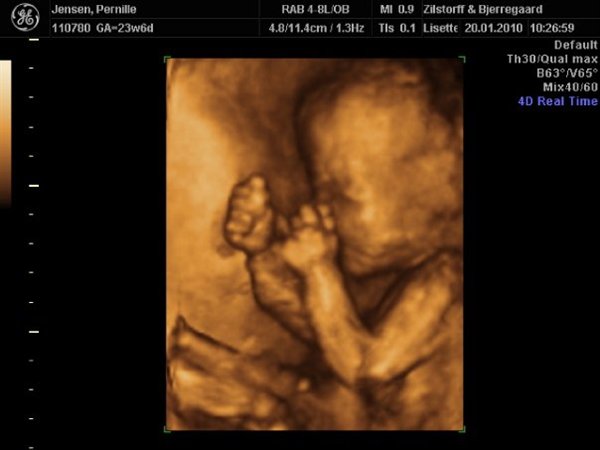

Jeg skal også selv til 3D scanning her d. 26/2

Der er jeg 30+1, er meget spændt på hvordan vores lille dreng ser ud, så tiden kan kun gå for langsom.

Jeg har selv valgt at få min scanning så sendt da jeg gerne ville kunne se ham så "færdig" som muligt